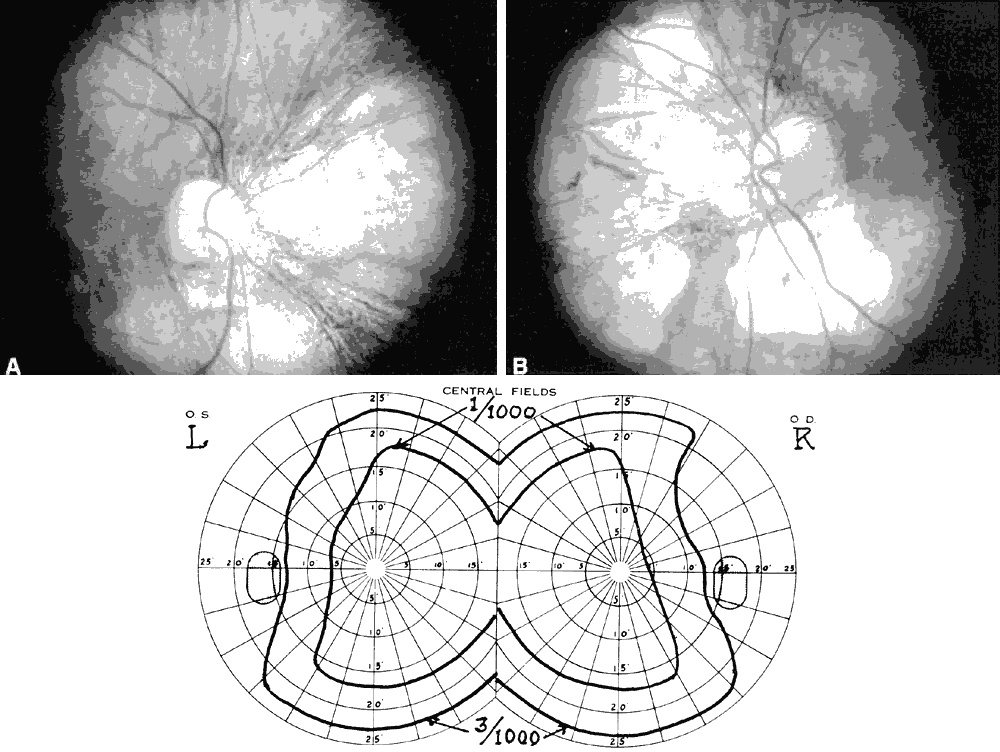

Hemianopic and quadrantic defects also occur in myopic eyes with posterior staphyloma. These defects are of importance as they may be mistaken as evidence of neurologic disease in those patients who have not had a careful fundus examination. The most common of these defects is bitemporal hemianopsia. This defect is produced by bilateral nasal staphylomas that arise at the optic nerves and involve the fundus areas nasal to it. Most frequently, these staphylomas are inferonasal. The resultant defect is initially relative and is because of ectasia of the affected fundus area. With the subsequent development of chorioretinal degeneration, the visual field will show corresponding absolute defects (Fig. 9). Relative field defects can be eliminated by retesting the affected field with increased minus power to correct for staphyloma depth.

Fig. 9. Fundus photographs of right (A) and left (B) eyes showing advanced myopic chorioretinal degeneration within nasal staphyloma of each eye. Visual field changes below suggest the presence of a chiasmal lesion.